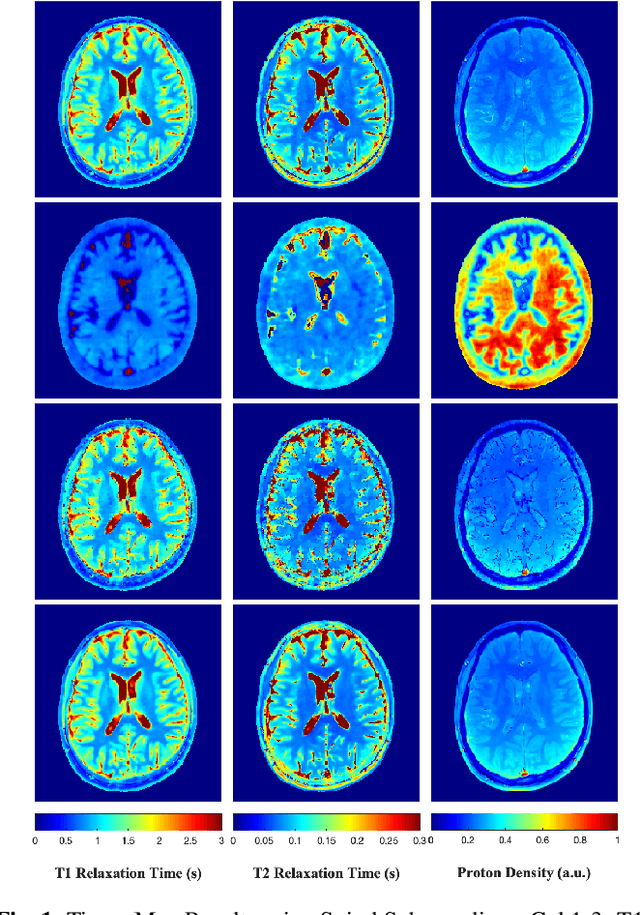

Abstract:Magnetic Resonance Fingerprinting (MRF) is a time-efficient approach to quantitative MRI, enabling the mapping of multiple tissue properties from a single, accelerated scan. However, achieving accurate reconstructions remains challenging, particularly in highly accelerated and undersampled acquisitions, which are crucial for reducing scan times. While deep learning techniques have advanced image reconstruction, the recent introduction of diffusion models offers new possibilities for imaging tasks, though their application in the medical field is still emerging. Notably, diffusion models have not yet been explored for the MRF problem. In this work, we propose for the first time a conditional diffusion probabilistic model for MRF image reconstruction. Qualitative and quantitative comparisons on in-vivo brain scan data demonstrate that the proposed approach can outperform established deep learning and compressed sensing algorithms for MRF reconstruction. Extensive ablation studies also explore strategies to improve computational efficiency of our approach.

Abstract:Magnetic Resonance Fingerprinting (MRF) is a time-efficient approach to quantitative MRI for multiparametric tissue mapping. The reconstruction of quantitative maps requires tailored algorithms for removing aliasing artefacts from the compressed sampled MRF acquisitions. Within approaches found in the literature, many focus solely on two-dimensional (2D) image reconstruction, neglecting the extension to volumetric (3D) scans despite their higher relevance and clinical value. A reason for this is that transitioning to 3D imaging without appropriate mitigations presents significant challenges, including increased computational cost and storage requirements, and the need for large amount of ground-truth (artefact-free) data for training. To address these issues, we introduce StoDIP, a new algorithm that extends the ground-truth-free Deep Image Prior (DIP) reconstruction to 3D MRF imaging. StoDIP employs memory-efficient stochastic updates across the multicoil MRF data, a carefully selected neural network architecture, as well as faster nonuniform FFT (NUFFT) transformations. This enables a faster convergence compared against a conventional DIP implementation without these features. Tested on a dataset of whole-brain scans from healthy volunteers, StoDIP demonstrated superior performance over the ground-truth-free reconstruction baselines, both quantitatively and qualitatively.

Abstract:The estimation of multi-parametric quantitative maps from Magnetic Resonance Fingerprinting (MRF) compressed sampled acquisitions, albeit successful, remains a challenge due to the high underspampling rate and artifacts naturally occuring during image reconstruction. Whilst state-of-the-art DL methods can successfully address the task, to fully exploit their capabilities they often require training on a paired dataset, in an area where ground truth is seldom available. In this work, we propose a method that combines a deep image prior (DIP) module that, without ground truth and in conjunction with a Bloch consistency enforcing autoencoder, can tackle the problem, resulting in a method faster and of equivalent or better accuracy than DIP-MRF.

Abstract:Current state-of-the-art reconstruction for quantitative tissue maps from fast, compressive, Magnetic Resonance Fingerprinting (MRF), use supervised deep learning, with the drawback of requiring high-fidelity ground truth tissue map training data which is limited. This paper proposes NonLinear Equivariant Imaging (NLEI), a self-supervised learning approach to eliminate the need for ground truth for deep MRF image reconstruction. NLEI extends the recent Equivariant Imaging framework to nonlinear inverse problems such as MRF. Only fast, compressed-sampled MRF scans are used for training. NLEI learns tissue mapping using spatiotemporal priors: spatial priors are obtained from the invariance of MRF data to a group of geometric image transformations, while temporal priors are obtained from a nonlinear Bloch response model approximated by a pre-trained neural network. Tested retrospectively on two acquisition settings, we observe that NLEI (self-supervised learning) closely approaches the performance of supervised learning, despite not using ground truth during training.

Abstract:Current spatiotemporal deep learning approaches to Magnetic Resonance Fingerprinting (MRF) build artefact-removal models customised to a particular k-space subsampling pattern which is used for fast (compressed) acquisition. This may not be useful when the acquisition process is unknown during training of the deep learning model and/or changes during testing time. This paper proposes an iterative deep learning plug-and-play reconstruction approach to MRF which is adaptive to the forward acquisition process. Spatiotemporal image priors are learned by an image denoiser i.e. a Convolutional Neural Network (CNN), trained to remove generic white gaussian noise (not a particular subsampling artefact) from data. This CNN denoiser is then used as a data-driven shrinkage operator within the iterative reconstruction algorithm. This algorithm with the same denoiser model is then tested on two simulated acquisition processes with distinct subsampling patterns. The results show consistent de-aliasing performance against both acquisition schemes and accurate mapping of tissues' quantitative bio-properties. Software available: https://github.com/ketanfatania/QMRI-PnP-Recon-POC

Abstract:Deep learning (DL) has recently emerged to address the heavy storage and computation requirements of the baseline dictionary-matching (DM) for Magnetic Resonance Fingerprinting (MRF) reconstruction. Fed with non-iterated back-projected images, the network is unable to fully resolve spatially-correlated corruptions caused from the undersampling artefacts. We propose an accelerated iterative reconstruction to minimize these artefacts before feeding into the network. This is done through a convex regularization that jointly promotes spatio-temporal regularities of the MRF time-series. Except for training, the rest of the parameter estimation pipeline is dictionary-free. We validate the proposed approach on synthetic and in-vivo datasets.